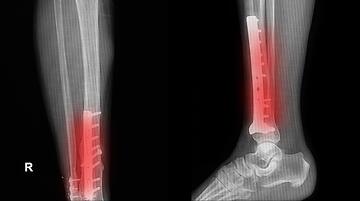

BONESUPPORT